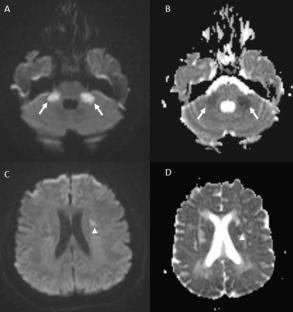

系统性红斑狼疮(SLE)是一种包括中枢神经系统在内的多器官累及的慢性自身免疫性疾病。神经精神表现(NPSLE)在很大比例的患者中观察到,可能包括缺血性中风,通常与抗磷脂综合征(APS)或小血管炎有关。我们报告的情况下,一个38岁的妇女谁提出了急性构音障碍和发烧的历史急诊科。脑成像显示双侧小脑中蒂和额区多发亚急性缺血性病变,弥漫性脑白质病。实验室检查显示高滴度的抗核、抗dsdna、抗心磷脂抗体和狼疮抗凝血剂。总体临床、放射学和免疫学特征与神经精神性SLE一致。缺血性事件的潜在原因可能是抗磷脂综合征和小血管炎。本病例强调了在双侧小脑中蒂病变鉴别诊断中考虑NPSLE的重要性。在这种复杂的临床情况下,早期识别和治疗NPSLE对于改善预后至关重要。

Systemic Lupus Erythematosus (SLE) is a chronic autoimmune disease with multiorgan involvement, including the central nervous system. Neuropsychiatric manifestations (NPSLE) are observed in a significant proportion of patients and may include ischemic strokes, often related to antiphospholipid syndrome (APS) or small vessel vasculitis. We report the case of a 38-year-old woman who presented to the emergency department with acute dysarthria and a history of fever. Brain imaging demonstrated multiple subacute ischemic lesions affecting the bilateral middle cerebellar peduncles and frontal regions, and diffuse leukoencephalopathy. Laboratory investigations revealed high-titer antinuclear, anti-dsDNA, anticardiolipin antibodies, and lupus anticoagulant. The overall clinical, radiological, and immunological profile was consistent with neuropsychiatric SLE. The possible underlying causes of ischemic events were antiphospholipid syndrome and small vessel vasculitis. This case highlights the importance of considering NPSLE in the differential diagnosis of diseases involving bilateral middle cerebellar peduncles. Early recognition and therapy of NPSLE are crucial for improving outcomes in this complex clinical scenario.